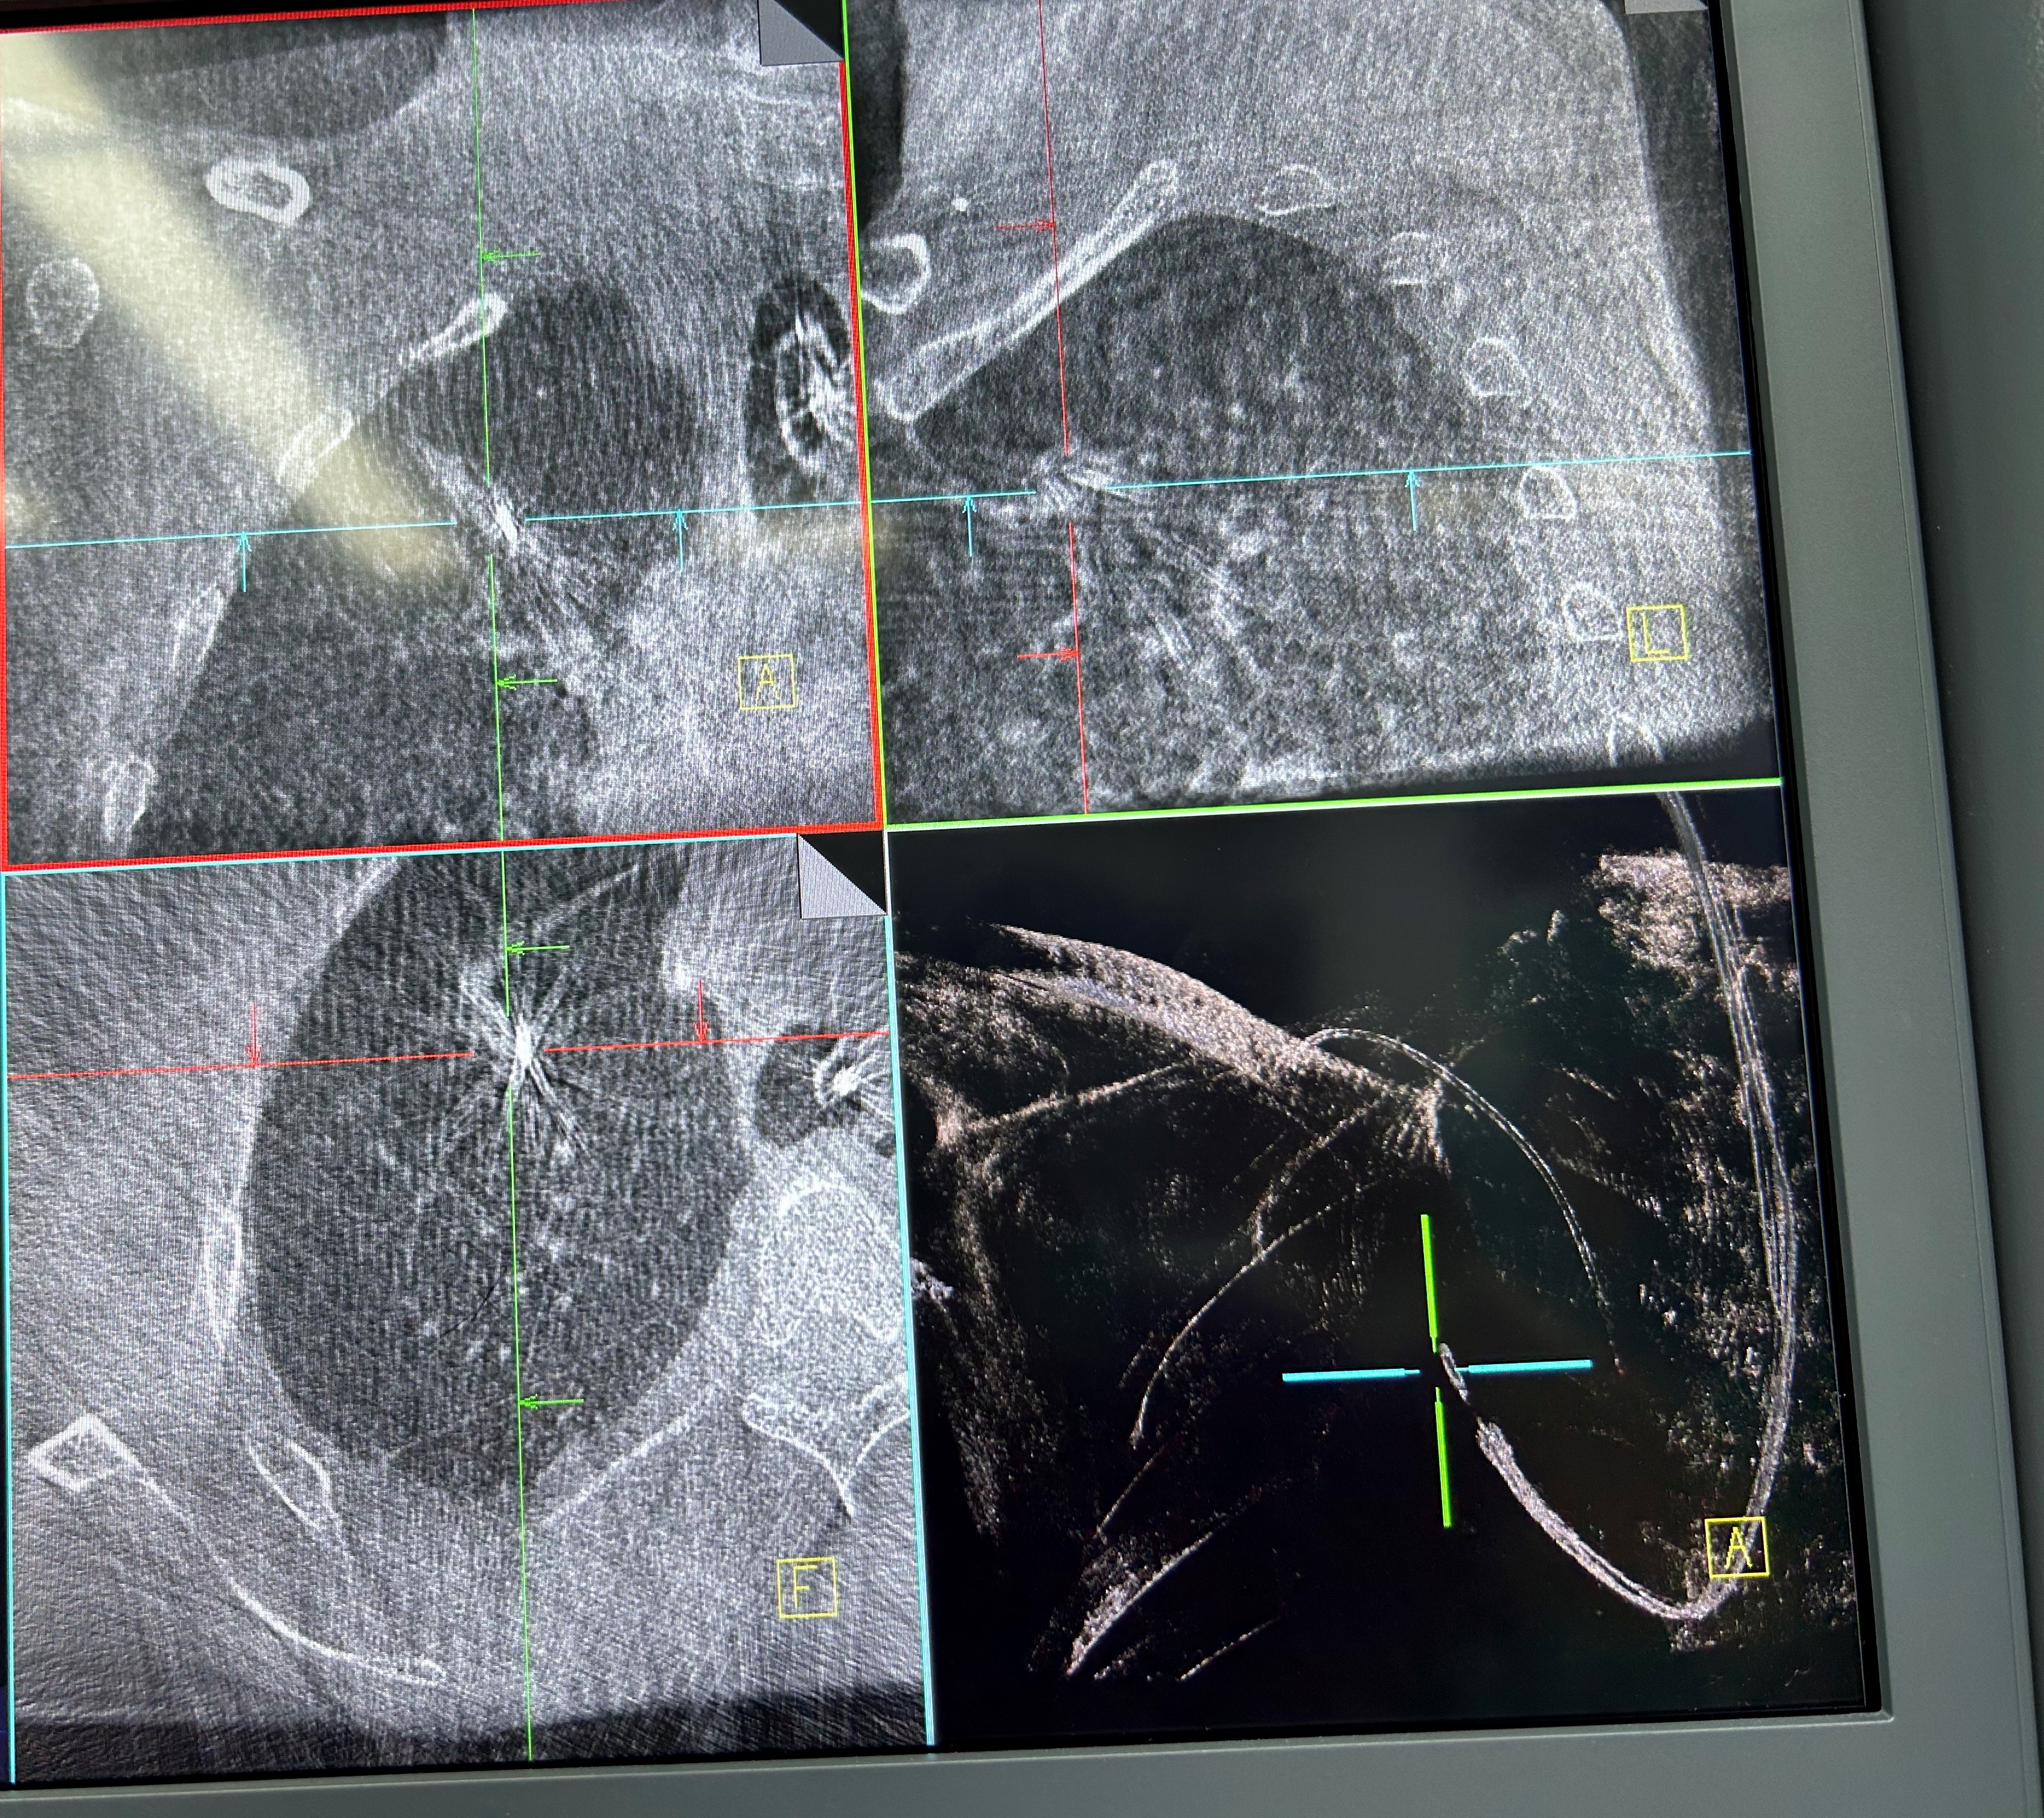

手术当日,呼吸科团队帮助患者在全麻下完成气管插管,手术由蒋军红主任指导,负责手术方案的实时优化与安全保障。曾大雄主任医师和王兰主任医师精准操作机器人支气管镜,在支气管镜导航机器人的精准引导下,通过AI三维重建、智能路径规划以及多模态信息融合,将支气管镜精准“引导”至右上叶尖段病灶处。随后,团队启动CBCT(锥形束计算机断层扫描)通过实时影像复核确认靶病灶,实现病灶“毫米级”精准锁定,彻底解决肺部病灶“找不到、找不准”的核心难题。机器人气管镜导航技术实现了从术前规划到术中操作全流程的智能精准控制,真正做到了肺部病灶的精准覆盖。

明确肿瘤诊断后,治疗方案即刻启动。团队经导航引导鞘管,精准插入一次性冷冻消融针(直径仅1.9mm)。再次通过CBCT确认消融针完全“扎根”于右上叶尖段病灶内后,开启冷冻治疗模式:以-160℃深低温冷冻10分钟、复温至45℃维持3分钟为一个治疗循环。完成了3次循环后,为确保病灶无遗漏,团队微调消融针位置,再次追加2次循环治疗。术后复查CBCT显示,病灶已呈现典型的冷冻后改变,术后两天复查胸部CT提示消融范围满意,治疗效果完全达到预期。整个手术过程中,患者生命体征始终平稳,术后第二天即可下床活动,真正实现了“微创治疗、快速恢复”的目标。

治疗前

治疗后